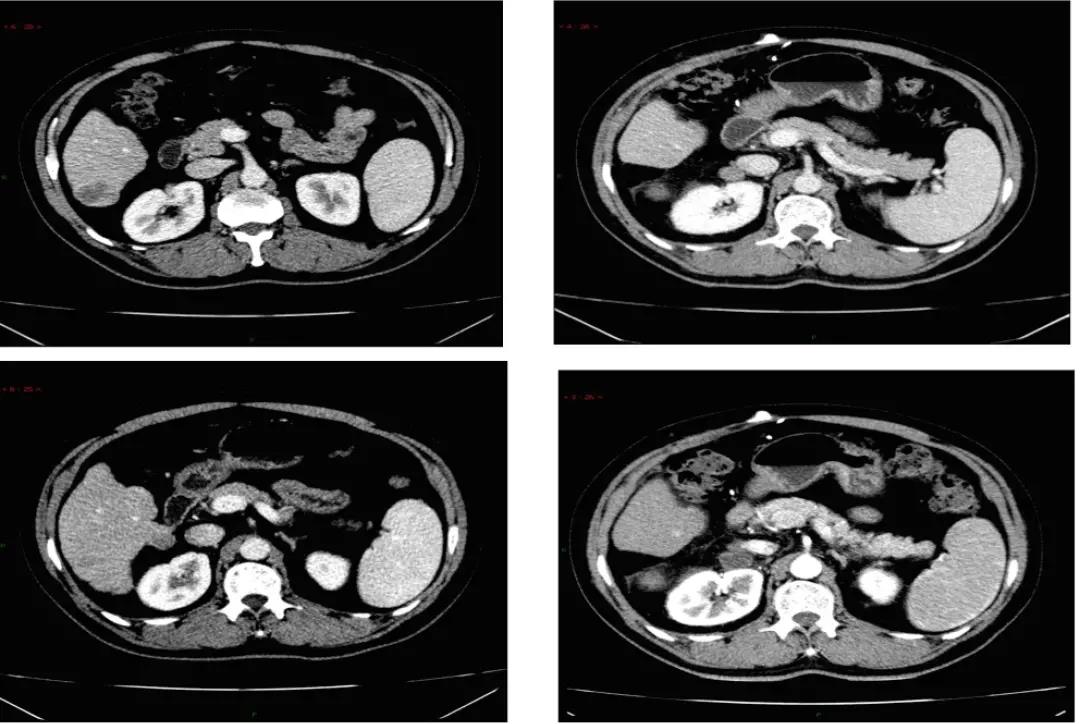

2019年2月25日随访发现肝内多发病灶复发,右上腹腹膜后淋巴结转移。MDT讨论后认为没有手术指征,分别于2019年2月27日及3月24日给予“TACE+经导管动脉内药物灌注术(TAI)”2次,术中造影提示肝肿块多发,血供丰富,行动脉灌注栓塞治疗,碘油10ml沉积好,同时动脉灌注奥沙利铂+氟尿嘧啶,为防止乙肝病毒复燃给予抗恩替卡韦规律抗病毒治疗,2程治疗后复查肝内病灶碘油沉积好,明显缩小好转,部分病灶消失,但监测到右上腹腹膜后淋巴结进展(图1)。因此于2019年3月28日患者开始口服索拉非尼片400mg BID。不良反应包括皮肤反应2级,伴疼痛、红肿,轻度乏力,纳差,对症处理可缓解,索拉非尼未减量。复诊评估疗效:疾病稳定(SD)。ECOG评分:0~1分。